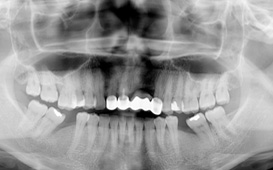

咬合崩塌 / 上牙下墜 / 下牙上長 / 前牙飆出 / 傾倒 / 蛀牙 / 牙周病缺牙未重建 - 臨床實例

上面的牙往下墜,下面的牙往上長,前面的牙往外飆 – 咬合崩塌牙周病,蛀牙;這些現象必然發生,時間越久,問題越大,而且除非藉由矯正及其他牙科治療,無法修正。

缺牙導致牙齒移位 - 臨床實例一